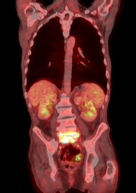

Infektionen der Wirbelsäule

Infektionen mit Bakterien treten hämatogen, das heißt ohne eindeutige erkennbare äußere Ursache auf. Ebenso können Keime von außen in den Körper eindringen, wie z. B. bei Operationen. Trotz höchster Sterilität ist dies nicht vollständig vermeidbar. Häufig betreffen Infektionen immunschwache oder ältere Menschen. Unbehandelt kann es neben der Zerstörung von wichtigen Strukturen zur Ausbildung einer allgemeinen Sepsis (Blutvergiftung) kommen, die lebensbedrohlich ist.

Infektionen erfordern häufig ausgedehnte oder radikale Operationstechniken mit dem Ziel der Beseitigung des krankhaften Gewebes, der Stabilisierung, Verbesserung der Lebensqualität durch Schmerzvermninderung und wenn möglich Ausheilung der Erkrankung. Häufig ist ein interdisziplinäres Vorgehen mit anderen Fachrichtungen erforderlich.